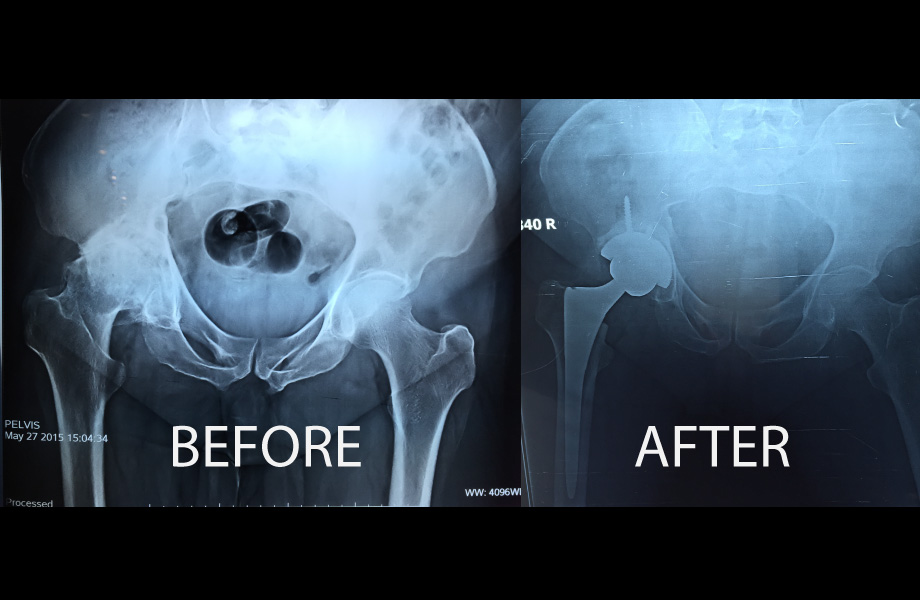

Hip Resurfacing